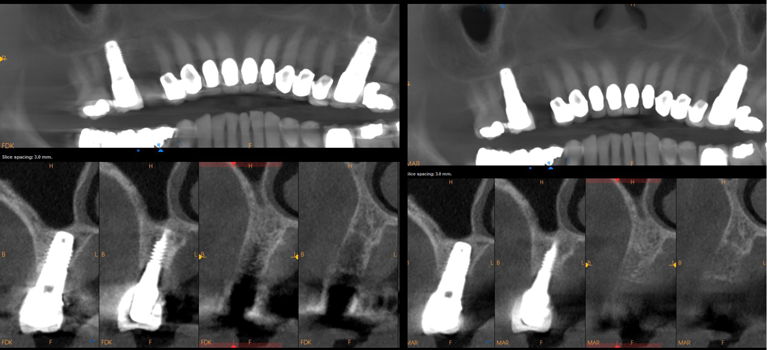

Often patients present with inadequate available bone for dental implant placement. Fig-

ure 8 depicts a 68-year-old male patient with two failing central incisors that required extraction. Before his visit with the author's practice, the patient had consultations with multiple clinicians and was given options of a dental bridge, a removable prosthesis, or dental implants that would have resulted in poor cosmetic outcomes.

After obtaining an initial CBCT image and IOS, it was apparent that there was a lack of available bone, a lack of buccal plate, and an excess of granulation tissue around the failing central incisors. Although immediate dental implantation was a potential option, the patient decided against this approach. A staged conservative approach was selected owing to the lack of available bone and extent of pathology that were exhibited by these incisors. Extractions and debridement followed by guided bone regeneration were performed. A large laminar membrane (Maxxeus; alternatively: Lamina®, Osteobiol®, Technoss Dental; Maxgraft® cortico, Botiss Dental, Straumann) anchored  by intraoral tacks aided in stabilizing the membrane and graft (Figure 9). The graft was covered with several layers of platelet-rich fibrin, and primary tension-free closure was obtained.

Four and a half months later, a new CBCT image (Figure 10) was captured, along with new IOS. Implant surgery was planned using planning software R2GATE®, MegaGEN; alternatively: Blue Sky Plan®, BlueSkyBio; RealGUIDE Plan, RealGUIDE) and a surgical guide was fabricated. A minimal flap approach was utilized for the placement of the two implants (AnyRidge®, MegaGEN; alternatively: Neodent® Grand Morse, Straumann; NobelReplace®, Nobel Biocare), and the implant sites were prepared using Densah burs (Figure 11). Torque and ISQ were recorded to assist in determining the timing for the final restorations. Struts extending from the surgical guide were designed in the location of the previously placed tacks, allowing for simple access and their removal. No immediate temporization was attempted; however, anatomically designed healing abutments were used to develop the soft tissues.

Fig 8. Top panel: Preoperative

CBCT. Note lack of alveolar bone for implant placement. Guided

bone regeneration is required to rebuild the site for future implant

placement. Bottom panel: Preoperative photograph reveals

unappealing esthetics of central incisors with elongated crowns.

Fig 10. Preoperative versus postoperative CBCT. Cross-sectional comparison between the preoperative and postoperative conditions at

4.5 months postoperatively is shown. Note the large amount of graft volume obtained creating a proper site for implant placement.